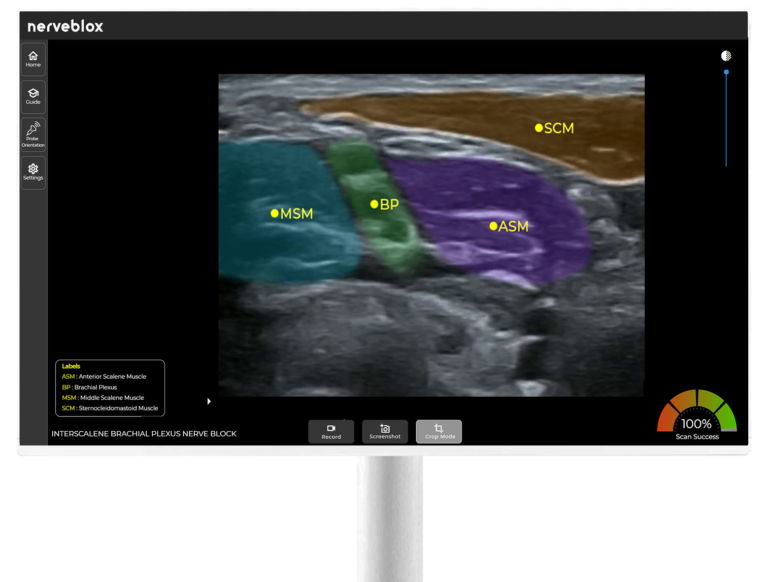

Nerveblox AI technology for ultrasound guidance is meticulously designed for anesthesiologists performing peripheral nerve block procedures and training. It is most valuable for applications requiring precision and those less frequent procedures that can be challenging due to their rarity – areas where AI capabilities outperform human attention. This versatility makes it an indispensable tool for highly skilled anesthesiologists who may require assistance with these uncommon procedures and peace of mind for image interpretation, especially regarding sonoanatomy.

Furthermore, our technology extends beyond anesthesiologists who are experts in ultrasound imaging. Anesthesiologists, including general practitioners, emergency medicine doctors, who may not possess specialized ultrasound training, can harness the power of our AI technology. Nerveblox provides standard, more accurate, and reliable peripheral nerve block guidance for them. This inclusivity ensures that anesthesiologists across all expertise levels can provide enhanced patient care through the utilization of advanced ultrasound technology tailored to peripheral nerve block procedures and training.